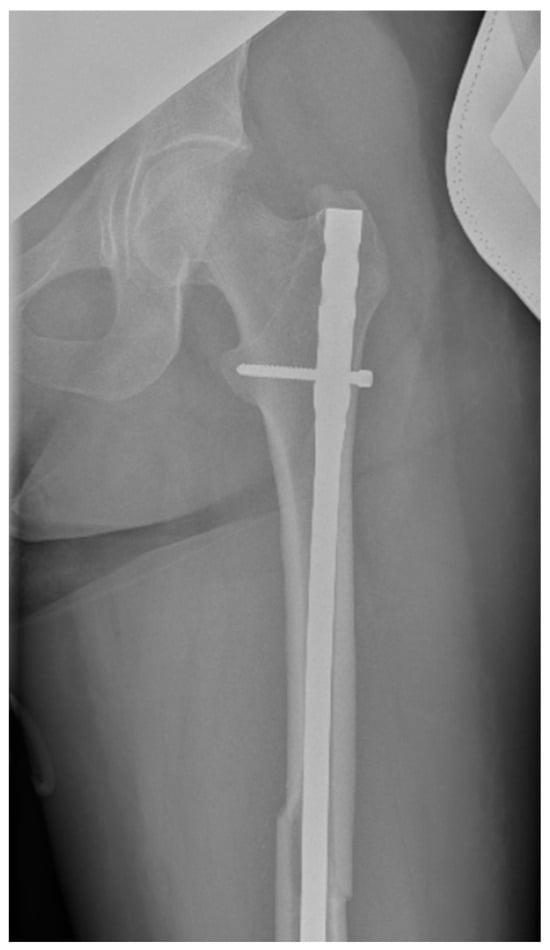

Radiographs (X-ray) of the left thigh were performed, under lead-apron protection on the abdominopelvic region, with the consent of the obstetrician. The radiation dose used during the X-ray was minimal. The total preoperative and intraoperative radiation dosage was 135.2 mGy. The diagnosis was a left mid-femoral diaphysis fracture with displacement (Figure 1).

Figure 1.

Profile X-ray of the left thigh revealing a fracture of the middle third of the femur with translation of the fragments.